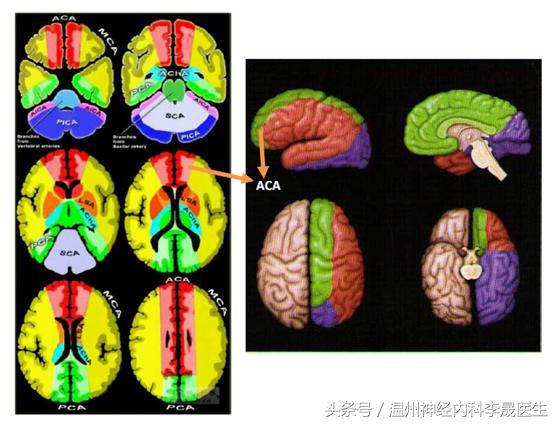

首先看看前动脉的供血区域,左图红色,右图绿色区域就是大脑前动脉的供血区域

细分前动脉的分支(关注我晚上发的大脑前动脉思维导图)

1)眶后动脉通常在前交通动脉前方4-5mm处与大脑前动脉主干呈锐角发出,越过直回后部入嗅沟内,分布至眶部后内侧

2)眶前动脉分布至眶前内侧部

3)额极动脉分布于额极内、外侧面

4)额前内侧动脉

5)额中间内侧动脉

6)额后内侧动脉

7)旁中央动脉

8)楔前动脉

9)胼胝体动脉